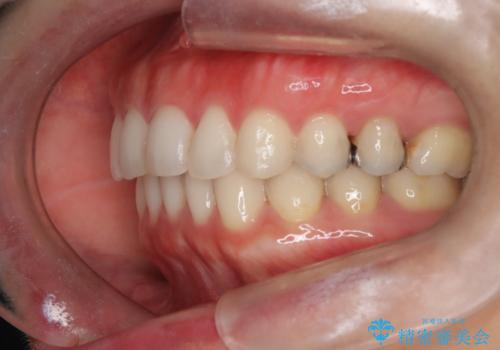

【下顎前歯の抜歯矯正】マウスピース矯正

- 下顎前歯の叢生を主訴に来院されました。

臼歯関係の状態から下顎前歯一本の抜歯を行う治療計画を立て、インビザラインを使用して治療を行いました。

今回の抜歯ケースはインビザラインでも綺麗に治ります。